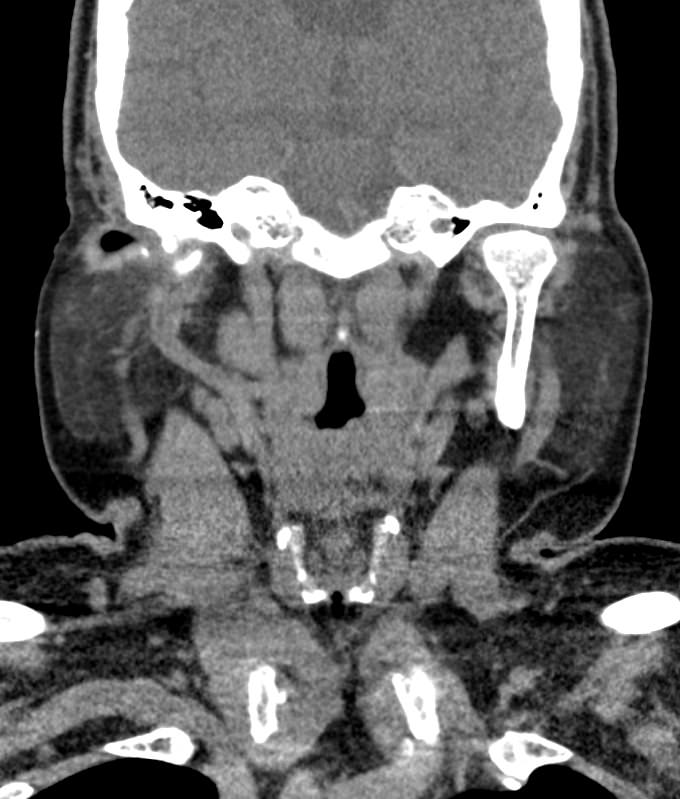

Мультиспиральная компьютерная томография – это высокоинформативный лучевой метод диагностики различной патологии мягких тканей шеи, включая воспалительные заболевания, травматические повреждения и опухолевые процессы. КТ позволяет оценить состояние щитовидной железы, паращитовидных желез, гортани, верхней части пищевода, шейных лимфоузлов и окружающих мягких тканей.

Метод КТ основан на применении рентгеновского излучения. Однако в отличие от обычного рентгена, при котором снимки производятся в одной плоскости, при КТ излучатель рентгеновских лучей постоянно двигается вокруг объекта исследования, проводя сканирование в различных плоскостях, а затем трансформируя полученные данные в цифровые трехмерные изображения. Это дает возможность визуализировать органы и ткани в мельчайших подробностях, а с помощью объемных 3D-реконструкций наглядно оценить пространственное расположение органов и патологических образований.

Рентгеновские лучи лучше всего поглощаются плотными структурами, такими как костная ткань. Поэтому кости хорошо видны на снимках КТ. Это делает компьютерную томографию незаменимой при необходимости обследования, в частности, костного скелета гортани. Однако для улучшения визуализации мягких тканей требуется введение специального контрастного препарата, поэтому КТ мягких тканей шеи в подавляющем большинстве случаев проводится с контрастным усилением.

Для контрастирования используется йодсодержащее контрастное вещество, которое в составе рентгеноконтрастного препарата вводится в вену пациенту непосредственно во время исследования. Благодаря способности контраста поглощать рентгеновские лучи на снимках КТ хорошо контрастируются кровеносные сосуды и опухолевые образования, имеющие, как правило, развитую сосудистую сеть. Методика внутривенного болюсного контрастирования помогает обнаружить воспалительные изменения, отличить доброкачественные опухоли от злокачественных, выявить поражение лимфатических узлов и степень прорастания опухоли в магистральные сосуды и окружающие ткани.